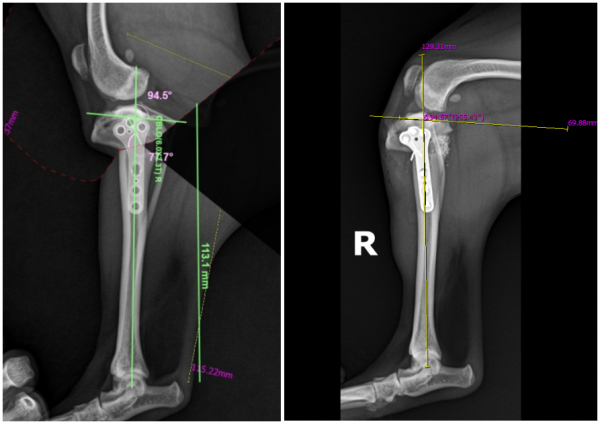

무엇보다 강아지 경골 기형 교정 수술(eTPA수술)과

같이 고난도 수술이 가능했던 건

수술 후 영상검사

사실 보기에는 쉬워보여도 주변에 근육과 인대가 많아서

정확히 수술하는 것은 매우 어려웠습니다.

그러나 수술 후 영상검사 시 정확하고 완벽하게 수술이 된 것을 확인할 수 있었습니다.

복돌이는 수술 후 건강하게 회복하고

현재는 뼈도 완전히 붙은 상태입니다.